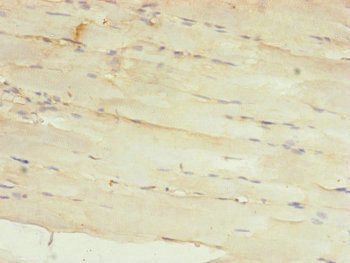

Immunohistochemistry of paraffin-embedded human skeletal muscle tissue using CSB-PA014908ESR2HU at dilution of 1:100